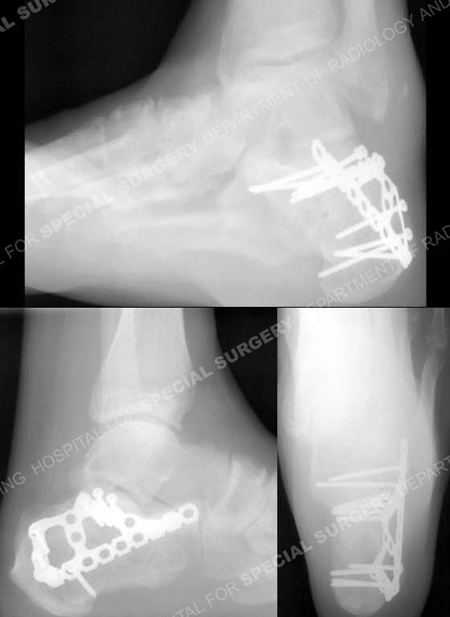

C Broden’s, lateral and Harris heel radiographs (counterclockwise from top) 5 years following fracture surgery

revealing a healed calcaneus fracture in excellent alignment.